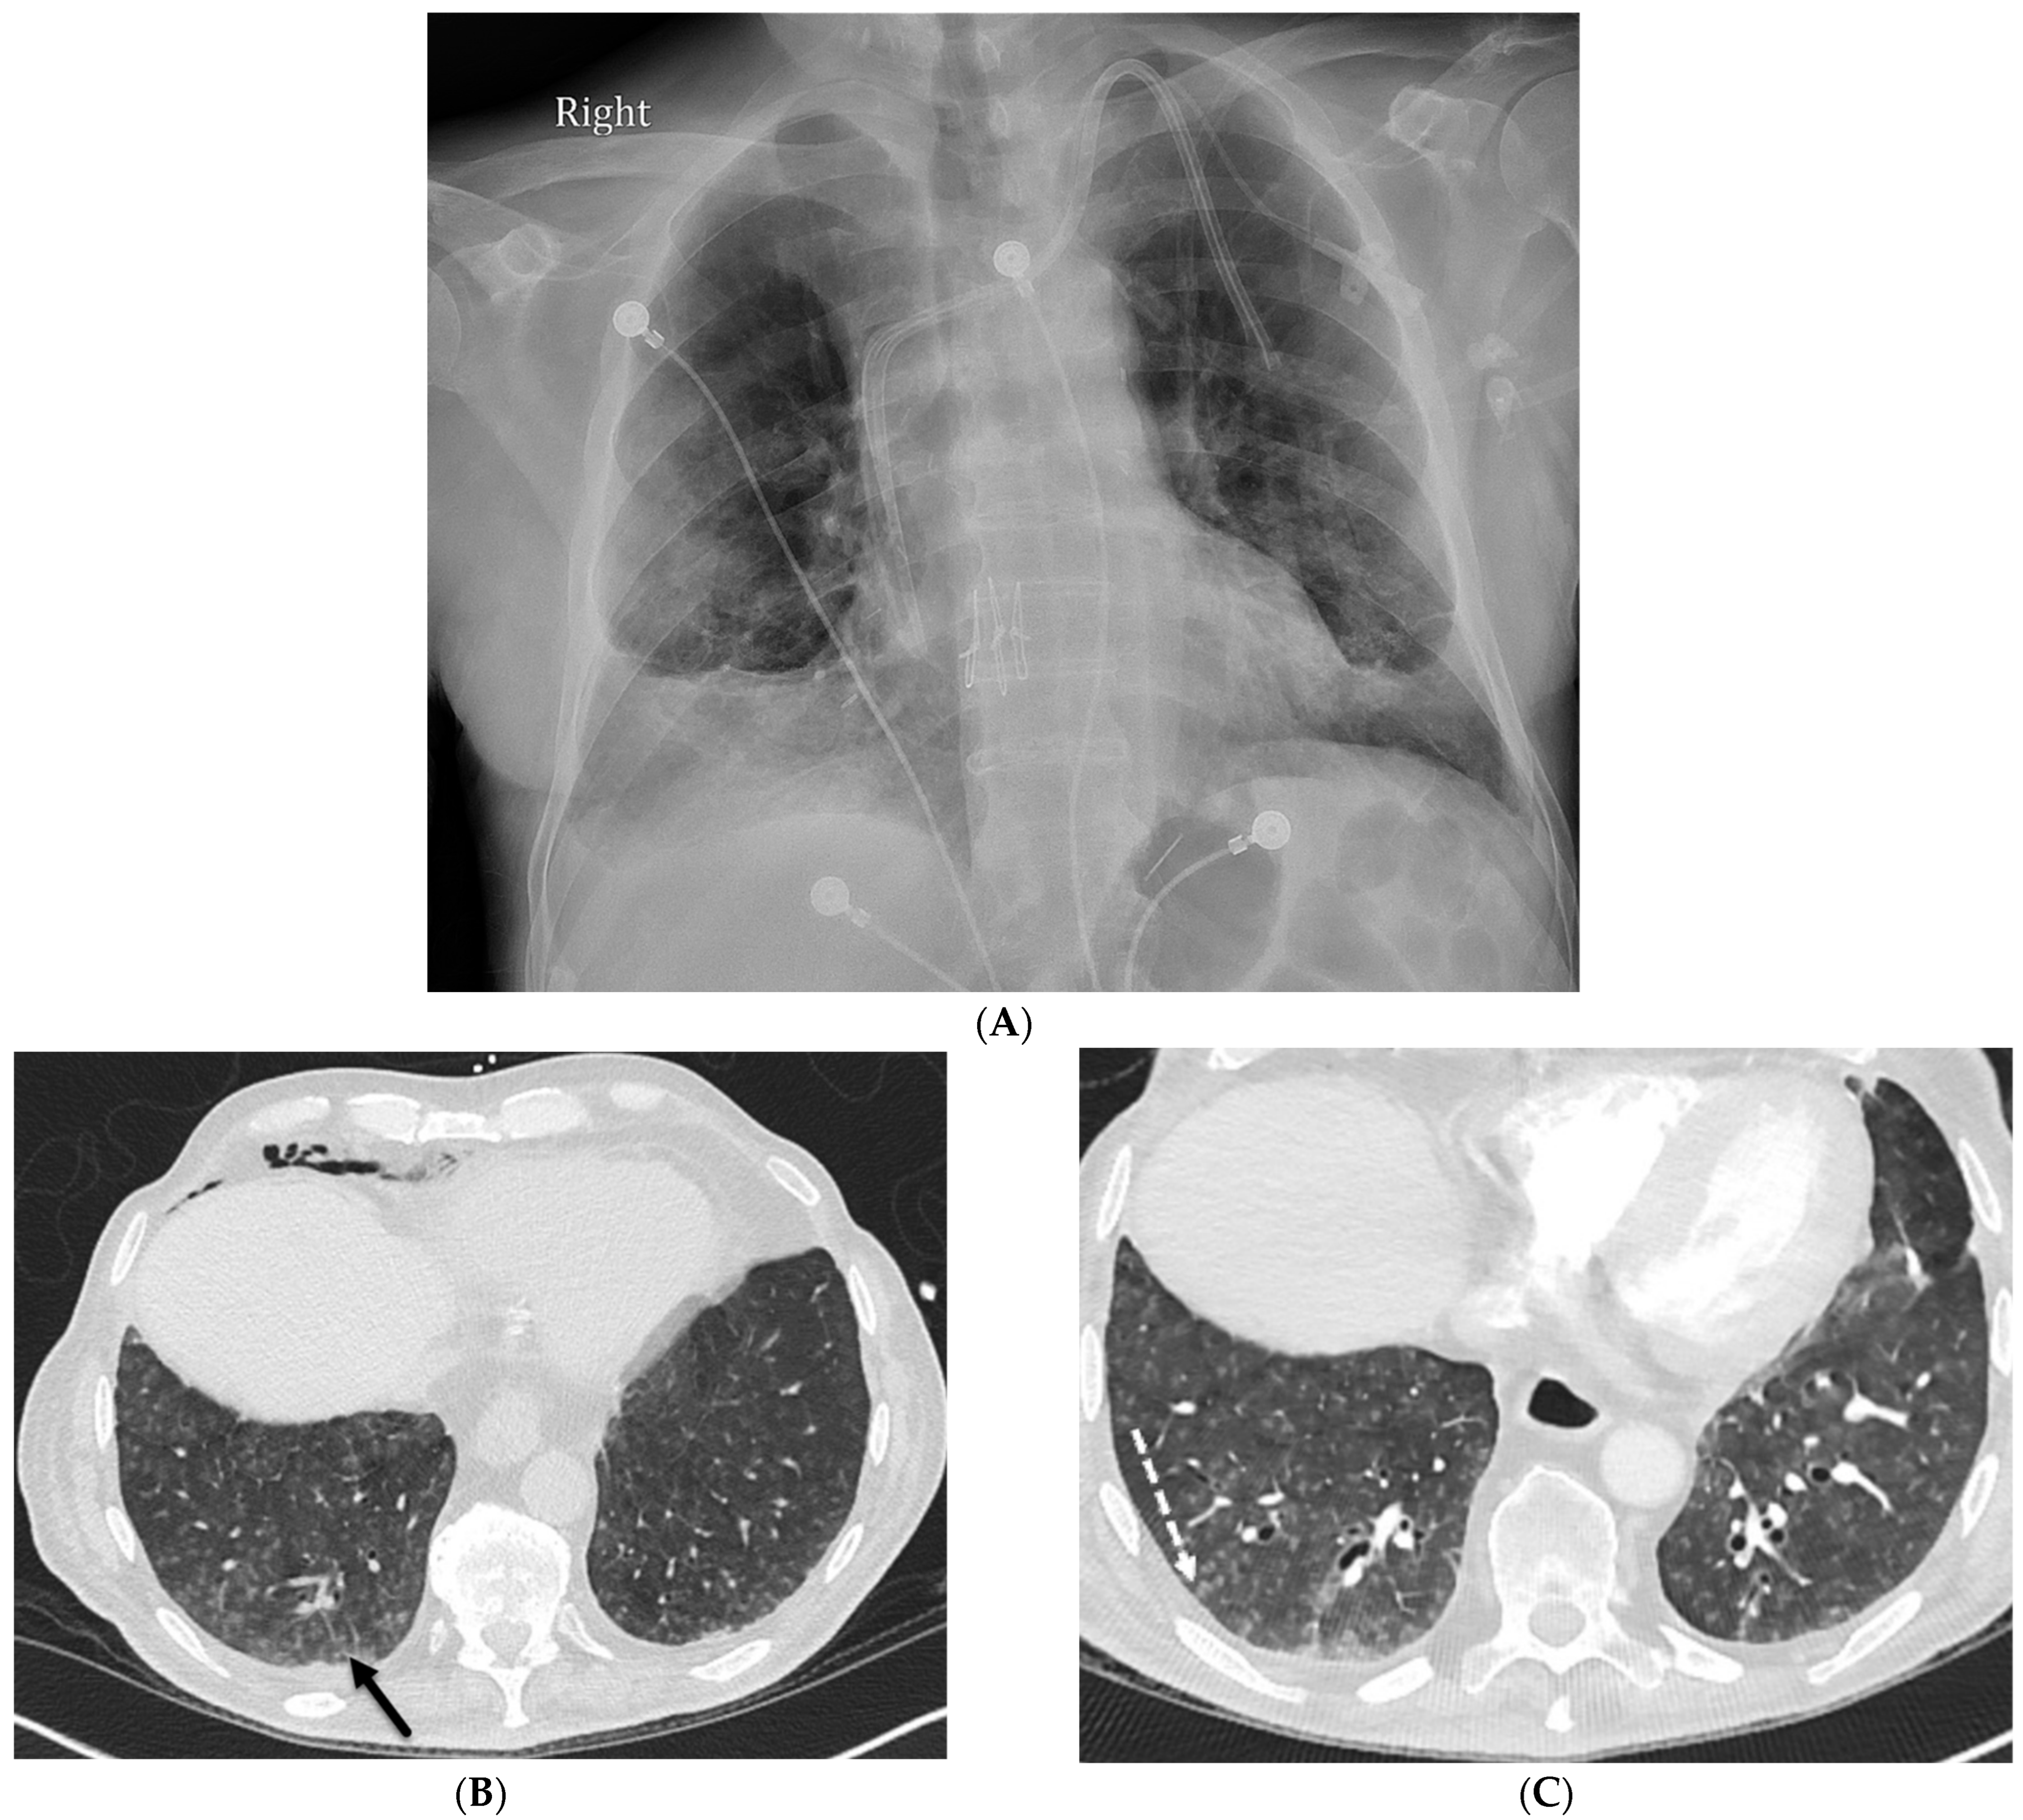

4.1. Lipoid Pneumonia

4.2. Drug-Induced Pneumonitis

4.3. Immunotherapy-Related Side Effects

4.4. Electronic Cigarette or Vaping Use-Associated Lung Injury (EVALI)